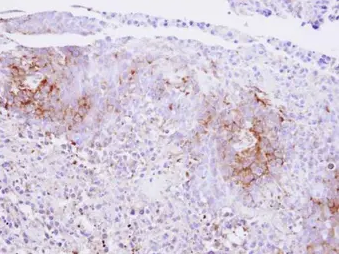

Immunohistochemical analysis of paraffin-embedded SAS xenograft , using Calcium Sensing Receptor antibody at 1:500 dilution.